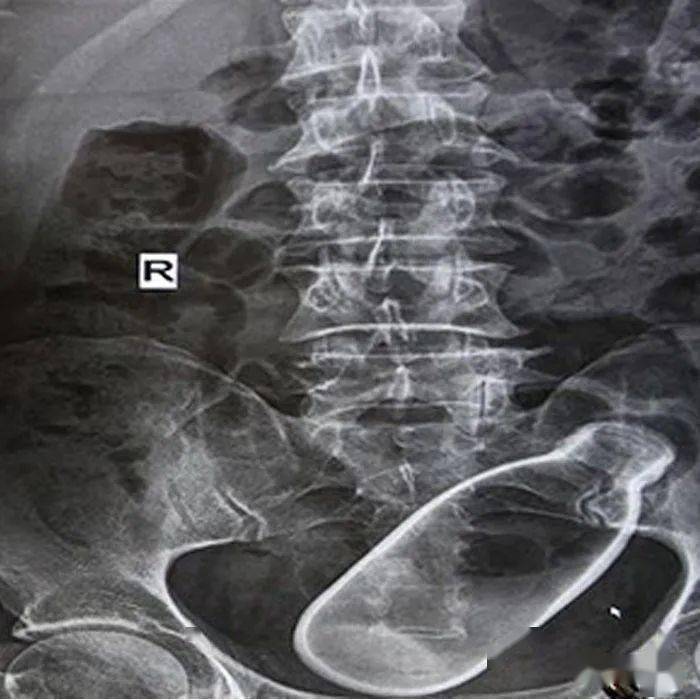

▷375mL的气泡饮料瓶